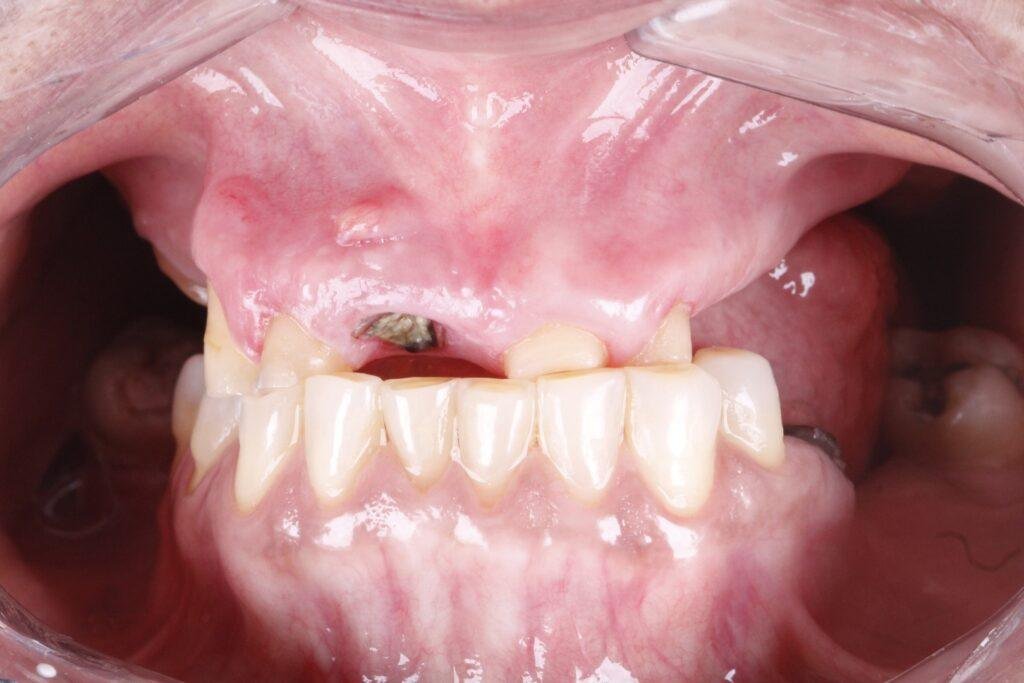

Veja alguns dos resultados obtidos através dos nossos tratamentos especializados.